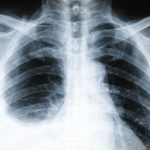

What you never knew about Pleurisy

pleurisy-image